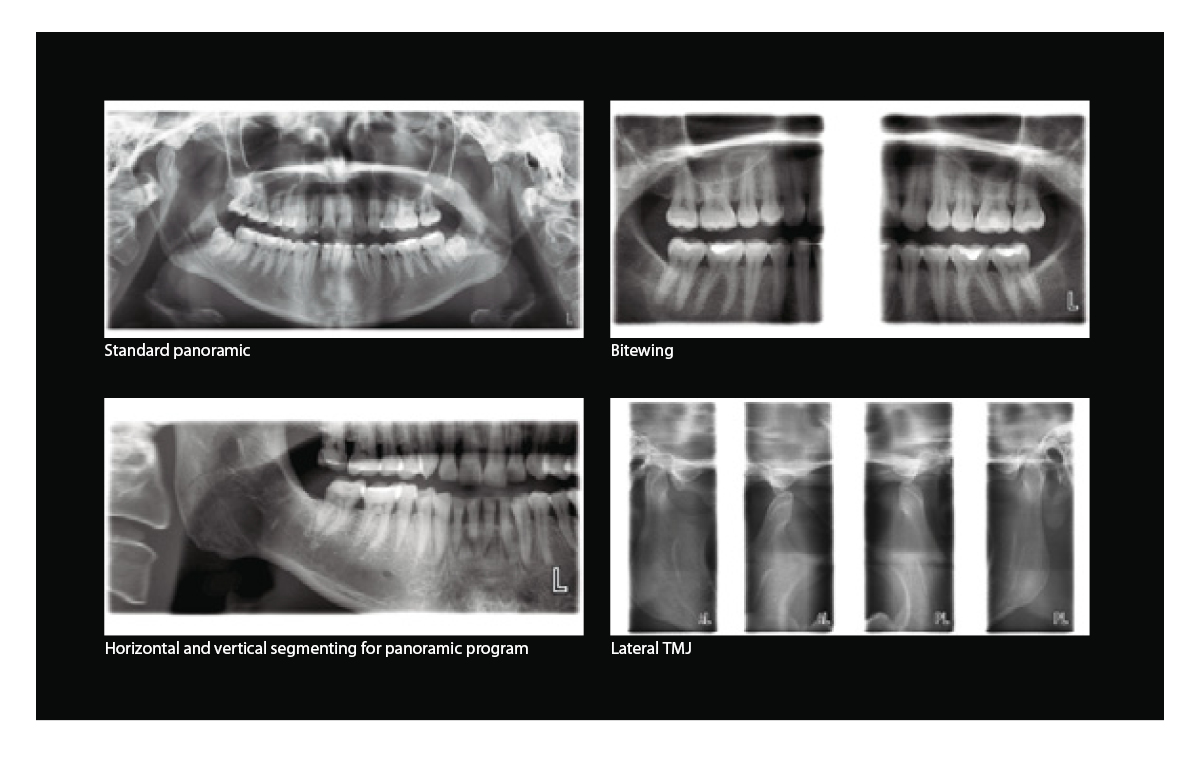

The three-joint Planmeca ProMax 2D S3 unit has been designed for all 2D imaging needs: panoramic, true extraoral bitewing, TMJ, sinus and 2D tomographic imaging.

While the two-joint ProMax 2D S2 panoramic imaging unit includes basic programs for panoramic, extraoral bitewing, TMJ and sinus imaging.

Extensive imaging programs

Planmeca ProMax 2D units offer the widest variety of imaging programs, including options for TMJ, sinus and tomographic imaging. The units also have a child mode that allows imaging at lower doses by reducing the imaging area and exposure values.